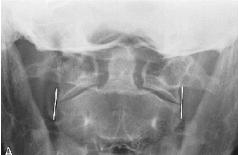

Q what is the name of this measurement? and what is the average + range?

A: Cervical Gravity Line

assesses the alignment of the odontoid process with the C7 body. line should pass through C7 body.